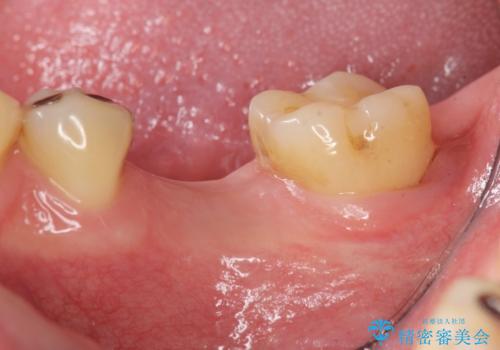

- 銀歯の奥歯で噛むと違和感・痛みがあるとのことで検査・治療を求めて来院されました。

銀歯を除去して見ると内部で虫歯が再発し、歯の辺縁は破折し保存が難しく抜歯をしなければいけない状態でした。

抜歯後ブリッジとインプラント治療を検討・相談し、より周囲の歯を削らずに済むインプラント治療を希望されたのでインプラントによる機能回復を計画します。